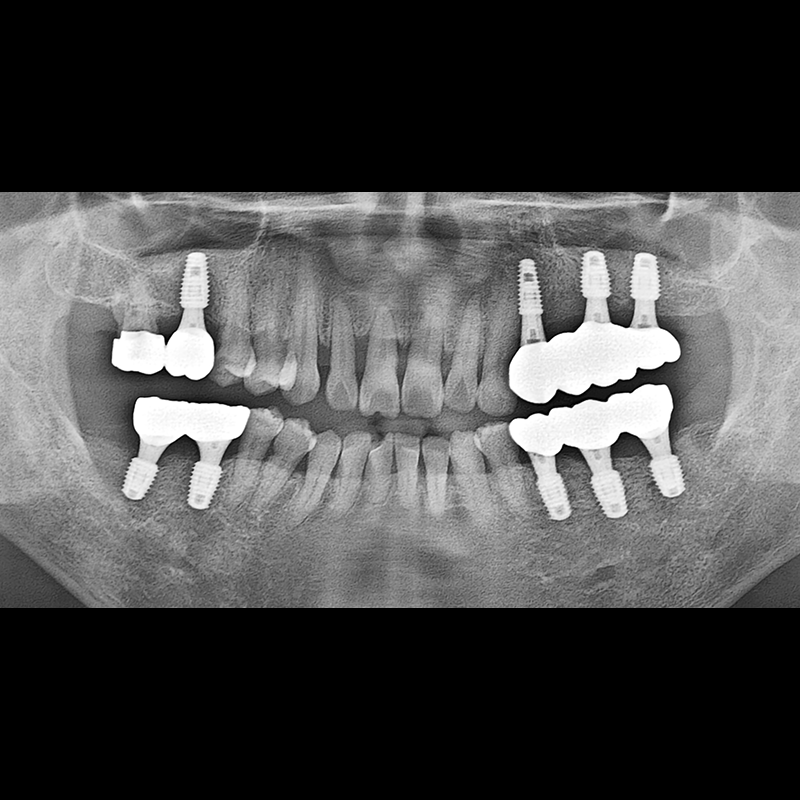

BEFORE AFTER

インプラント手術事例 2025.05.30

欠損した歯の部分と、生かしにくい歯の位置にインプラントを植立しました。